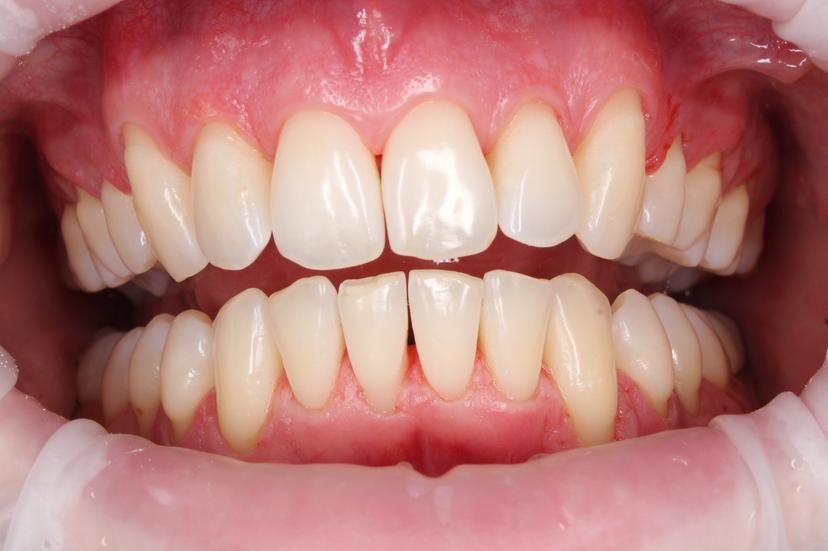

Во время процедуры был удален пигментированный зубной налет и камень, а также проведена полировка зубов.

Во время процедуры удален пигментированный зубной налет и камень, проведена полировка зубов.